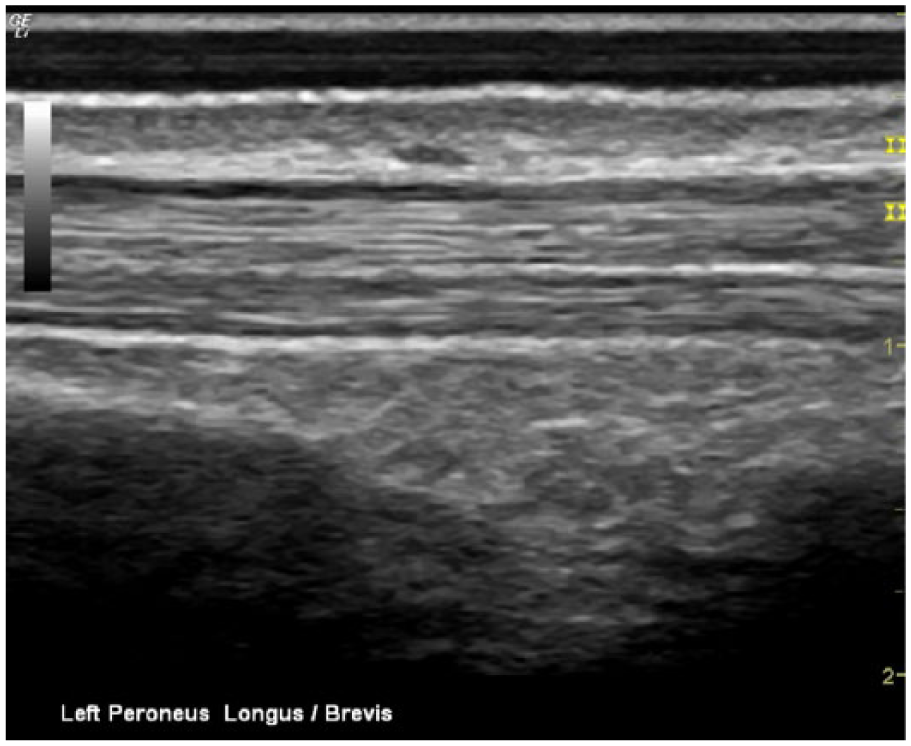

Long-axis sonogram showing the normal, asymptomatic left peroneus longus and peroneus brevis tendons.